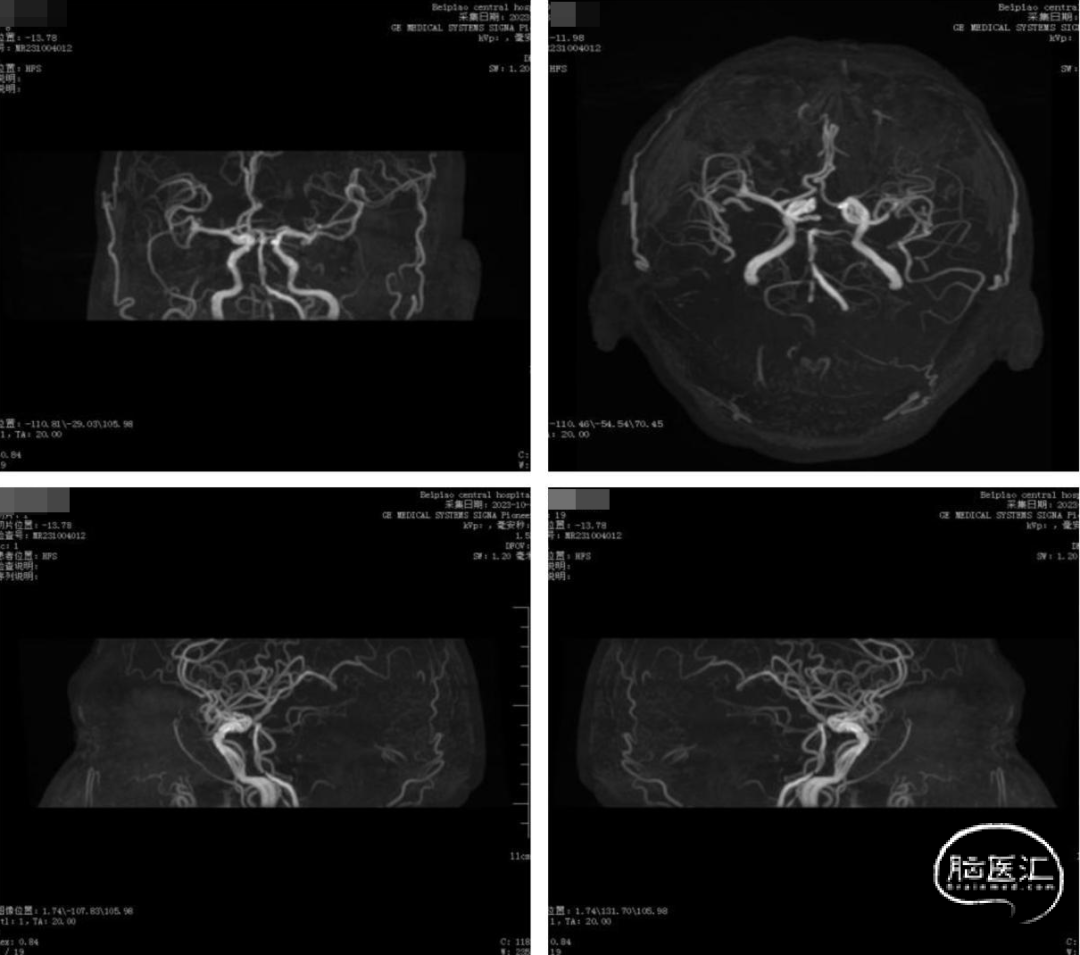

术前头部DWI、MRA提示:未见新发脑梗死病灶,右侧椎动脉纤细,左侧椎动脉优势,双侧椎动脉V4段重度狭窄。

术前造影示:右侧椎动脉纤细,左侧椎动脉优势,起始部走形迂曲。